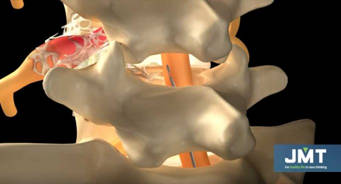

Cuando tenemos una hernia discal que nos está provocando una ciática se va a producir inflamación, esta inflamación provoca edema y que se produzcan adherencias entre la raíz y el disco. Una raíz nerviosa que no puede acompañar los movimientos de la espalda por que está adherida es dolorosa. Después de una cirugía de columna el proceso natural de cicatrización puede atrapar a esa raíz nerviosa y comprimirla.

La epidurolisis consiste en introducir un catéter a través del canal espinal, a través de este catéter podemos llegar al lugar exacto donde se encuentra la lesión e introducir medicación. Además al introducir líquido a presión conseguiremos romper las adherencias y la fibrosis.